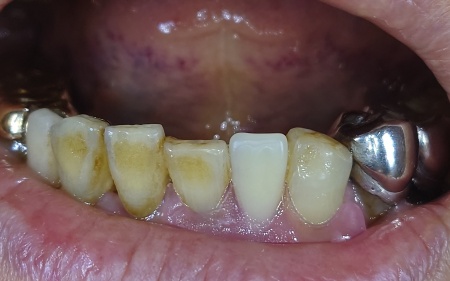

拝見したところ、左上の4番目の歯(第1小臼歯)の根が割れて、痛みと歯ぐきの炎症が認められました。

まず、左上の歯を抜歯します。

続いてインプラント埋入手術を実施し、インプラントを正しい位置と角度であごの骨に埋入しました。

インプラントがあごの骨にしっかりと定着したことを確認してから、型取りを行いインプラントの上に取り付ける人工歯を作製します。